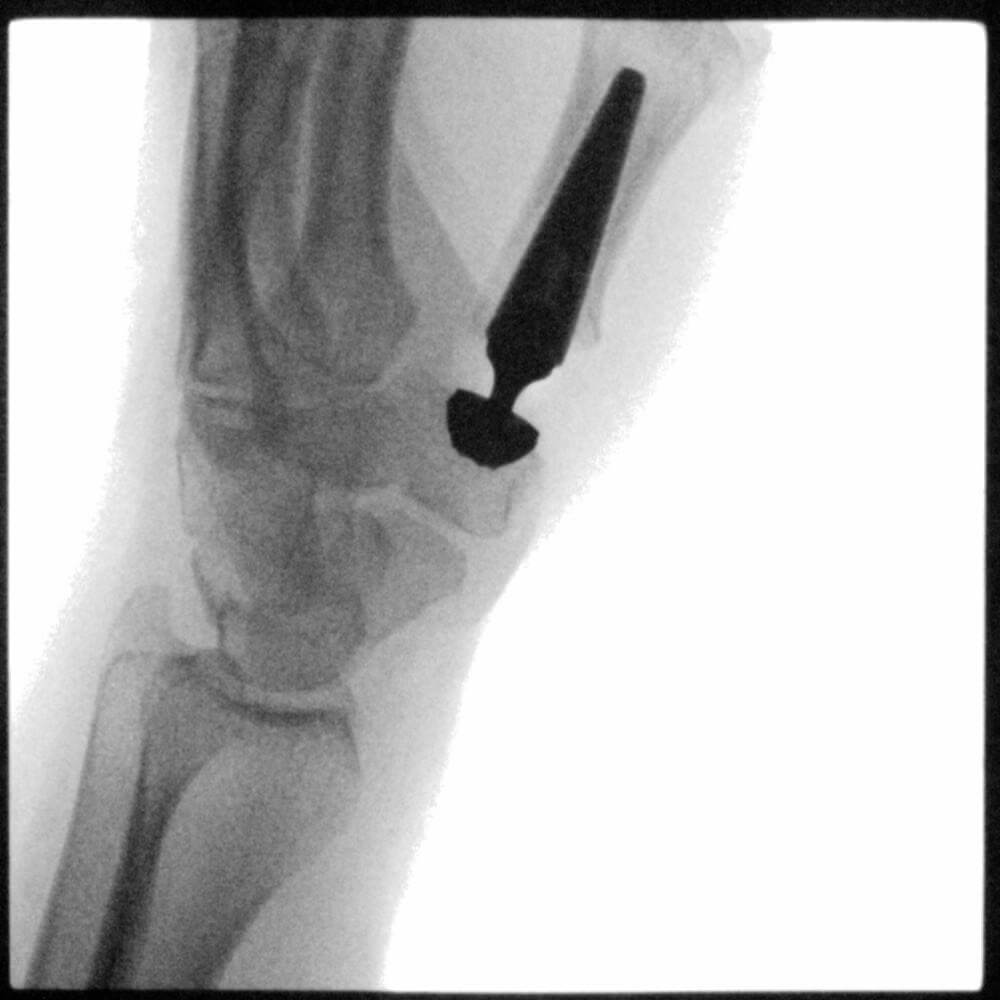

Seit meiner Ausbildung widme ich mich in meiner Arbeit und Forschung intensiv der Handchirurgie. Somit kann ich Ihnen das gesamte Spektrum der konservativen und operativen Behandlung von Hand- und Unterarmerkrankungen anbieten. Als Unfallchirurg habe ich mich auf die Versorgung von handnahen Verletzungen spezialisiert. Als Orthopäde widme ich mich der Versorgung von abnützungsbedingten Erkrankungen der Gelenke sowie Sehnen- und Nervenerkrankungen.